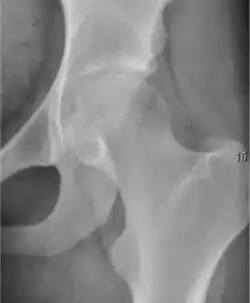

- Slipped capital femoral epiphyses (SCFE)

Slipped capital femoral epiphyses (SCFE) usually affect 11- to 14-year-old adolescents (Figure 4). Radiographs may show widening and irregularity of the physis and posterior inferior displacement of the capital femoral epiphysis. On the AP view Klein’s line, tangent to the lateral aspect of the femoral neck, does not intersect the femoral head indicating that it is displaced. SCFE may compromise the blood supply to the femoral head and cause avascular necrosis, mainly when there is instability between the fragments.[1]

-

Figure 4: (a) X-ray of a 10-year-old child with left hip pain. It was considered normal at emergency despite the widening of the left physis (arrow). Two weeks later epiphysiolysis was evident (b). Despite appropriate surgical reduction (c) osteonecrosis developed and femoral head collapsed 1 month later (d).[1]